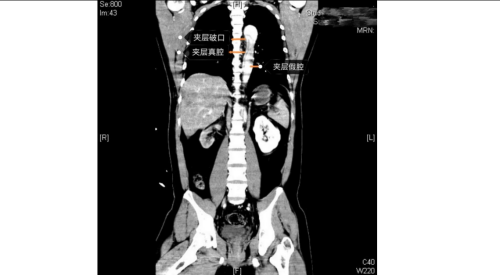

立博体育 急诊科、麻醉手术科、外周血管介入科、急诊重症监护室等多学科团队火速响应。外周血管介入科主任、主任医师赵扬程及团队迅速评估患者病情并果断决定立即急诊手术。赵扬程指出,影像显示患者主动脉内膜严重撕裂,血流冲入血管壁形成巨大“假腔”。危急的是,夹层广泛累及腹腔主干血管,导致双下肢血管完全撕闭,下肢冰冷。此时主动脉壁薄如蝉翼,分秒间可致命破裂!同时,下肢及腹腔脏器严重缺血,如不迅速开通血管,将迅速引发肢体坏死、多器官衰竭。

手术室内,患者血压一度飙至惊人的320/150mmHg,循环濒临崩溃!麻醉团队全力稳定循环。在患者下肢几乎无法触摸到脉搏的极端条件下,外周血管介入科主任赵扬程及团队迎难而上,凭借精湛技术,精准置入支架,成功封堵主动脉内膜巨大破口,并精细重建了主动脉弓部受累的重要分支血管,恢复关键血流。这场持续近3小时的手术每一步都高风险且高度紧张,如同在死神面前进行“拆弹”。最终,这颗“血管炸弹”被成功拆除。